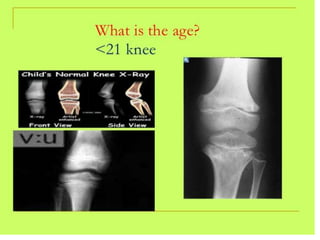

Late Puberty

• Females: 13 years to 15 years of age

• Males: 14 years to 16 years of age

• Assessments of skeletal maturity in this stage

are primarily based on the degree of

epiphyseal fusion of the distal phalanges.

• Fusion of the epiphyses to the metaphyses in

the long bones of the hand tends to occur in

an orderly characteristic pattern, as follows

1) Fusion of the distal phalanges;

2) Fusion of the metacarpals;

3) Fusion of the proximal phalanges; and,

4) Fusion of the middle phalanges.

Post-puberty

• Females: 15 years to 17 years of age

• Males: 17 years to 19 years of age

• At this stage, all carpals, metacarpals and

phalanges are completely developed, their

physes are closed

• assessments of skeletal maturity are based on

the degree of epiphyseal fusion of the ulna and